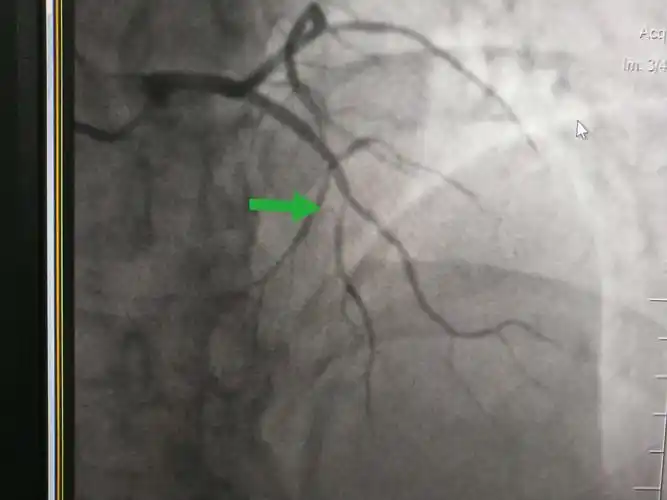

冠脉造影提示:左冠状动脉的前降支也有重度狭窄